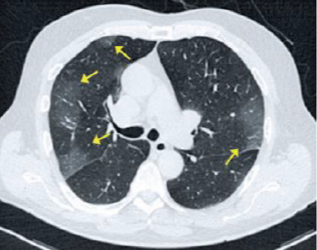

Paciente de 72 anos apresenta anosmia, febre e tosse há 3 dias. A principal hipótese diagnóstica é Covid-19. Quais achados na imagem tomográfica a seguir corroboram para esse diagnóstico?

Enunciado 4535182-1